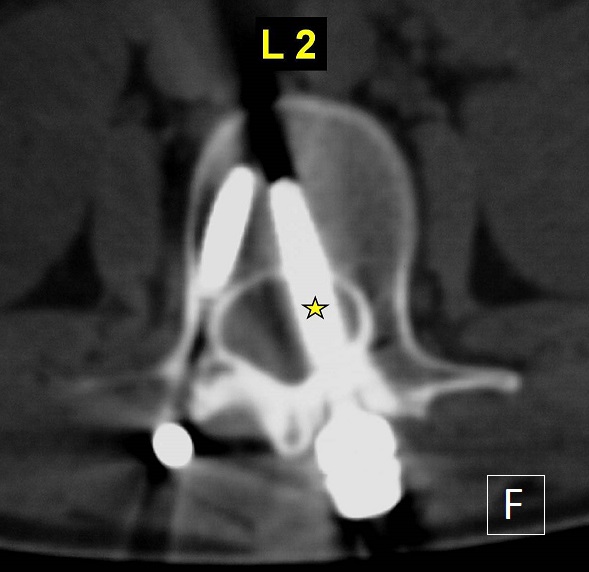

Pedicle screws are the main type of instrumentation used in the lumbar spine via the posterior approach. The accuracy of their insertion is always a concern because the malposition of screws is associated with a potential risk of iatrogenic injury of any neurovascular structure they pass. Fortunately, spinal cord and cauda equina injuries are rare. This 18-year-old paraplegic woman presented more than one year after a posterior spinal fusion (extended from L2 to L5 using mono-axial pedicle screws and rods) was performed at another institution following a spinal injury. She complained of atypical mild pain to the lumbar spine, while plain radiographs were suspicious for a L2 left transpedicular screw misplacement. Lumbar spinal CT-scan demonstrated a misplaced L2 left transpedicular screw which penetrated the spinal canal. The patient and her family were concerned about the intra and perioperative risks of the procedure and denied any further intervention at the moment. Late detection of pedicle screw misplacement into the spinal canal is exceptional and the complexity of revision surgery should be balanced especially if the patient presented with a total paraplegia since the first traumatism. To prevent these serious surgical complications, the surgeon must have a clear understanding of the anatomy of the affected pedicles and to use some imaging guidance (fluoroscopy or radiographs).